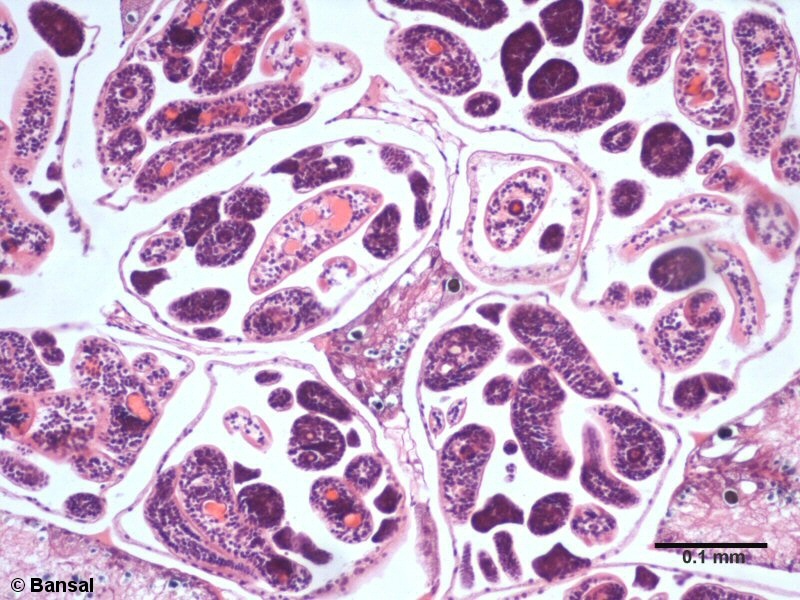

Clonorchis sinensis

Chinese liver fluke or oriental liver fluke / douve de Chine

cross section (EN) / coupe transversale (FR)

(EN) : Histopathological section (Hematoxylin-eosin staining) of the bile duct from a host showing infection by the liver fluke.